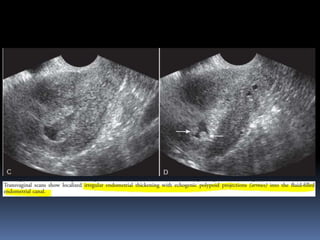

This document contains an image gallery from Dr. Mohit Goel showing various uterine anomalies and ovarian cysts. It includes images of an arcuate and unicornuate uterus, endometritis, a twisted ovarian pedicle, dermoid cysts of varying sizes and echogenicity containing hair, fat, and calcifications, and a combination dermoid cyst showing both mesh and plug structures. The gallery provides ultrasound images of different gynecological conditions for medical education and reference.